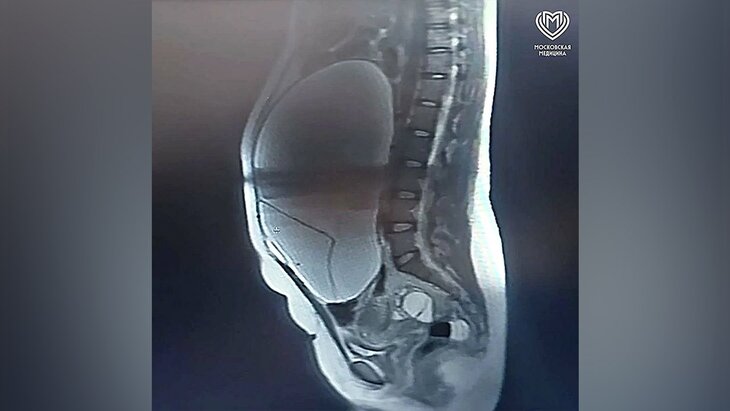

Врачи в Москве спасли женщину с опухолью размером с баскетбольный мяч